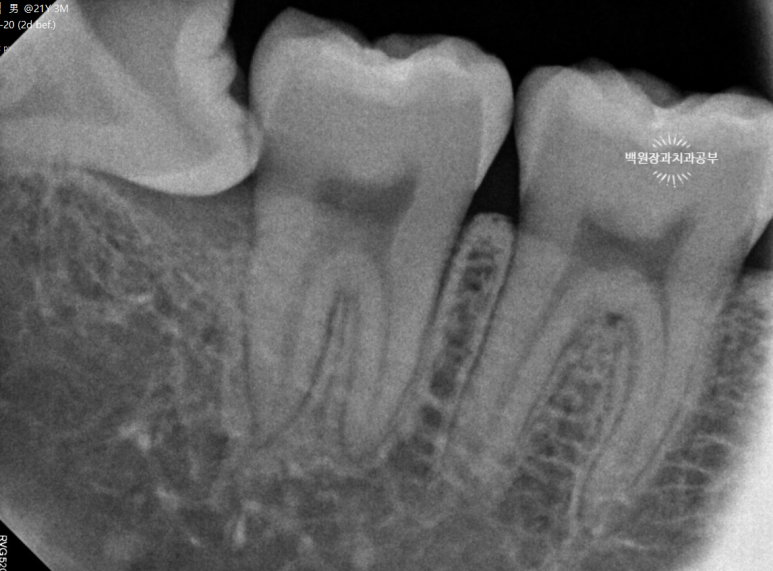

보다 확대된 치근단 방사선사진을 보시면, 누워있는 사랑니가 아의 치아에 끝이 걸려있는 것을 보실 수 있을거에요.

절대 그냥 뽑히지 않습니다. ㅎㅎ 치아를 나눠서 제거하는 것이 훨씬 쉬워요!